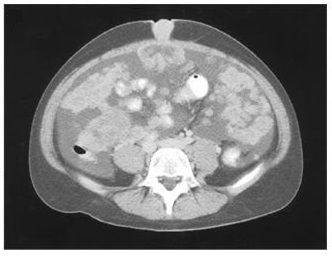

Computed tomographic scanning showed a large pelvic mass probably originating from the ovary, omental and hepatic metastases, ascites, and a mass through the umbilicus (image).